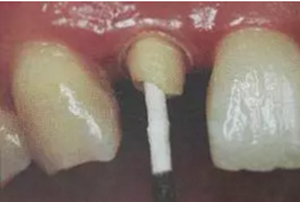

根管內(nèi)涂抹粘接劑時(shí),理想的粘接劑層厚度為25um - 40um,厚度增加或不均勻不利于纖維樁的順暢就位,多余的粘接劑的存在會(huì)加速樹脂水門汀的固化速度。

(粘結(jié)劑涂擦20s,涂抹2-3層)

(紙尖吸出多余粘結(jié)劑)

根管內(nèi)涂抹粘接劑的較規(guī)范操作應(yīng)是:毛刷蘸取粘接劑在根管內(nèi)反復(fù)涂擦20s,涂抹2-3層,然后用紙尖吸取干凈,氣槍吹5s使粘接劑中的溶劑快速揮發(fā)。此操作中,大錐度吸潮紙尖非常關(guān)鍵,它不僅可以吸取多余的粘接劑,同時(shí)也可使粘接劑在根管內(nèi)鋪展均勻。醫(yī)生朋友不要“忽視小物件鑄成大事件。